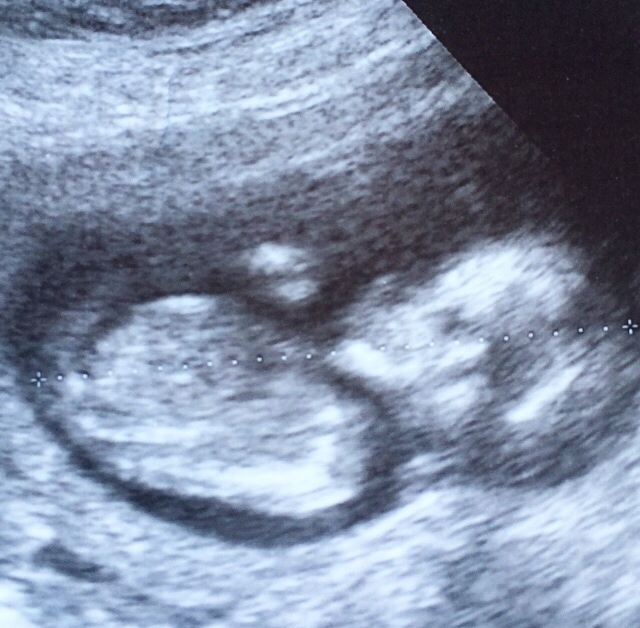

Hi again ladies! I posted a shot of my baby at 12+6 a few days ago but it wasn't really clear. I got this photo today at 13+3 and was wondering if there are any clues? Attachment 23055